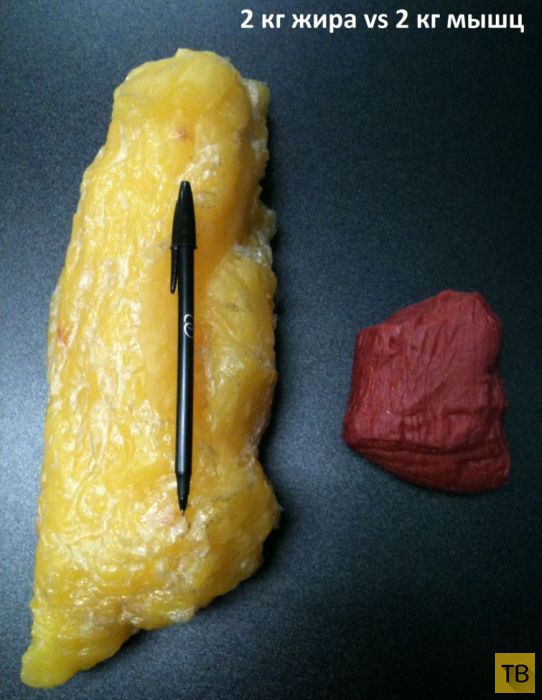

2 кг жира по сравнению с 2-мя килограммами мышц

2 кг жира по сравнению с 2-мя килограммами мышц